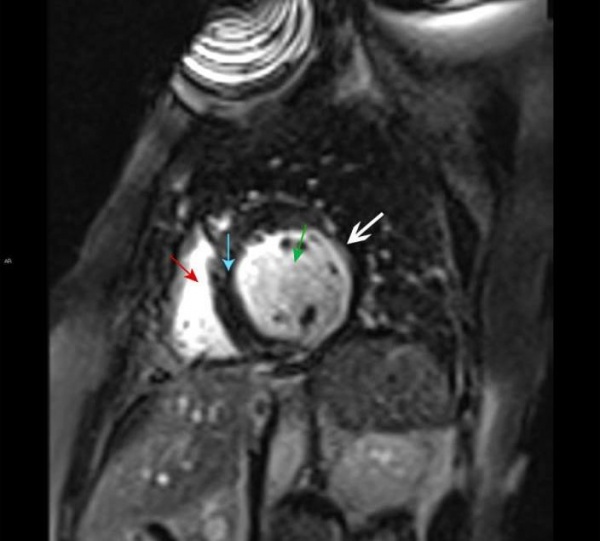

МРТ сердца. Правый желудочек (красная стрелка), левый желудочек (зеленая стрелка), межжелудочковая перегородка (синяя стрелка). Позднее контрастное усиление субэндокардиальной зоны левого желудочка, характерное для инфаркта миокарда (белая стрелка).